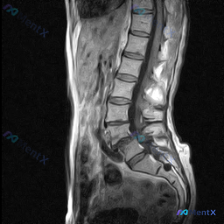

整理到一份病例影像资料,有点意思,放出来和大家讨论下读片思路。 首先说明:这是一张腰椎矢状位T2WI MRI,用户最初问的是「能不能看到脊柱侧弯」。 先把影像里能看到的点列一下: - 从L1/L2到L5/S1,椎间盘T2信号都低了,髓核高信号基本没了,典型「黑盘征」 - L4/L5、L5/S1椎间盘...

整理了一份影像分析讨论素材,大家先别着急看预设答案,聊聊第一眼思路: 用户一开始问的是「这张图片明显可见的病症是脊柱侧弯吗」,但提供的只有腰椎MRI T2加权矢状面这一个序列。 先把影像里能看到的客观表现列出来: 1. 椎间盘:全腰椎T2信号普遍减低(黑盘征),L4/5、L5/S1椎间隙变窄,且有明...

整理了一份腰椎影像资料,先跟大家同步一下情况: 用户提到了“脊柱侧弯”,但目前手里只有腰椎MRI-T2序列的矢状位影像,没有冠状位的片子。 先说说这份矢状位上能看到的点: 1. 多节段椎间盘T2信号减低,L2/3、L3/4、L4/5、L5/S1都有“黑盘”征 2. L4/5明显向后突,压到硬膜囊前缘...